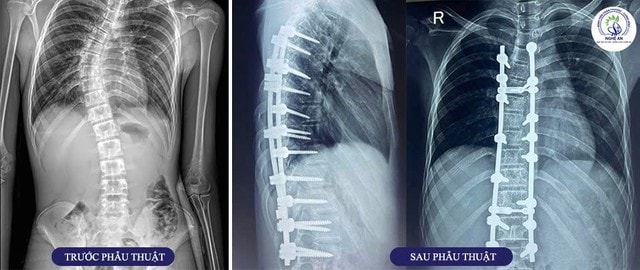

Bệnh nhân nam 16 tuổi, quê ở Thanh Chương – Nghệ An được chẩn đoán vẹo cột sống ngực – thắt lưng vô căn tuổi thiếu niên (AIS), với các chỉ số: góc vẹo Cobb 45 độ, Risser độ IV – giai đoạn phát triển xương gần hoàn tất. Biến dạng ảnh hưởng đến tư thế, thẩm mỹ và tiềm ẩn nguy cơ chèn ép thần kinh, giảm dung tích sống phổi nếu không được can thiệp kịp thời.

Ca phẫu thuật do BSCKII Nguyễn Hoàng Dương – Trưởng khoa Phẫu thuật Thần kinh – Sọ não – Cột sống trực tiếp chỉ đạo và thực hiện cùng ê-kíp. Phẫu thuật được thực hiện qua đường sau, với kỹ thuật chỉnh hình và cố định cột sống bằng hệ thống vít – thanh nẹp; bao gồm: 15 vít qua cuống sống vùng ngực – thắt lưng, 2 thanh dọc phục hồi trục giải phẫu, 2 thanh ngang tăng cường ổn định, xương ghép nhân tạo hỗ trợ hàn xương liên bản sống.

Quá trình phẫu thuật diễn ra an toàn, lượng máu mất trong giới hạn cho phép, không cần truyền máu.

Sau phẫu thuật chỉnh hình và cố định cột sống kết hợp tập phục hồi chức năng chuyên sâu tại Bệnh viện Chấn thương Chỉnh hình Nghệ An, cột sống bệnh nhân thẳng trục hơn, gần như hết vẹo; tình trạng đau lưng giảm rõ rệt, sinh hoạt dễ dàng hơn và cải thiện về thẩm mỹ.